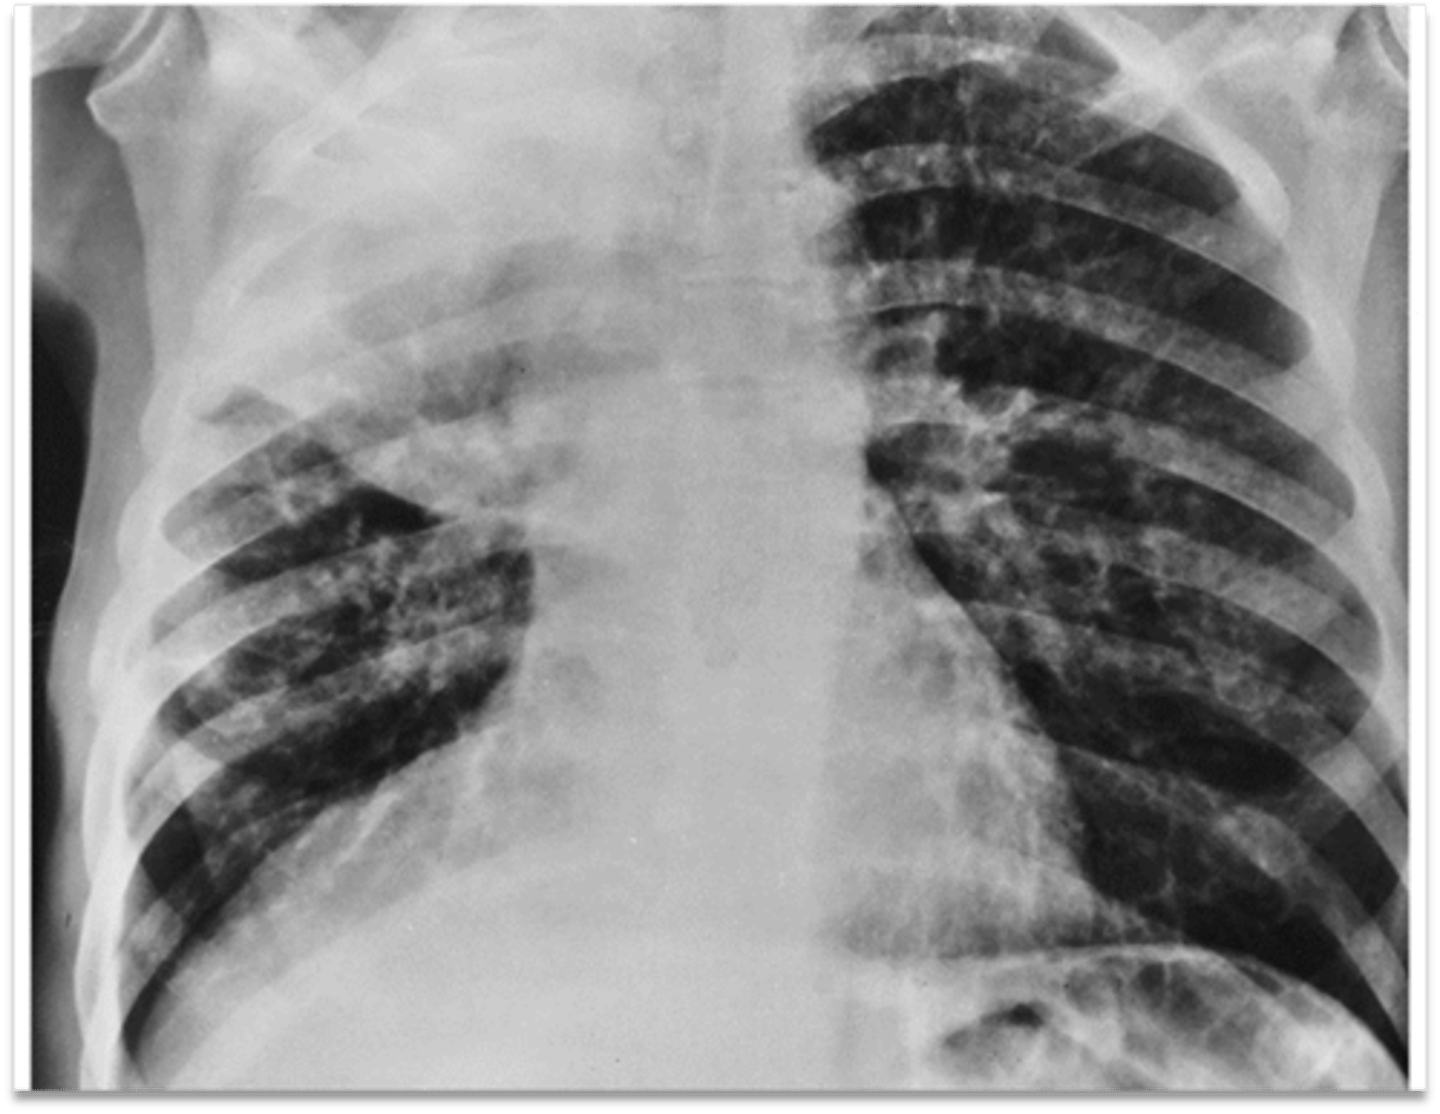

Left lung

Where is the abnormality located in the chest?

Atelectasis

What is the red arrow indicating?

Effusion

What is the likely interpretation?